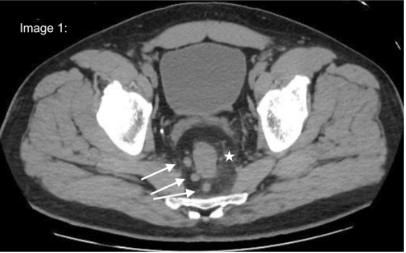

Physical examination had no alterations besides worsening pain with deep palpation in the referred areas. Cell blood count and comprehensive metabolic panel were normal, only C-reactive protein was increased. A Computerized Tomography scan (Figure 1) presented significant parietal thickening of the lower rectum, with densification of mesorectal fat and adjacent lymph nodes enlargement. He was admitted for further investigation and pain management. Inflammatory bowel disease and infective colitis were initially suspected.

Figure 1: White arrows-enlarged lymphnodes White star-densification of meso-rectal fat.